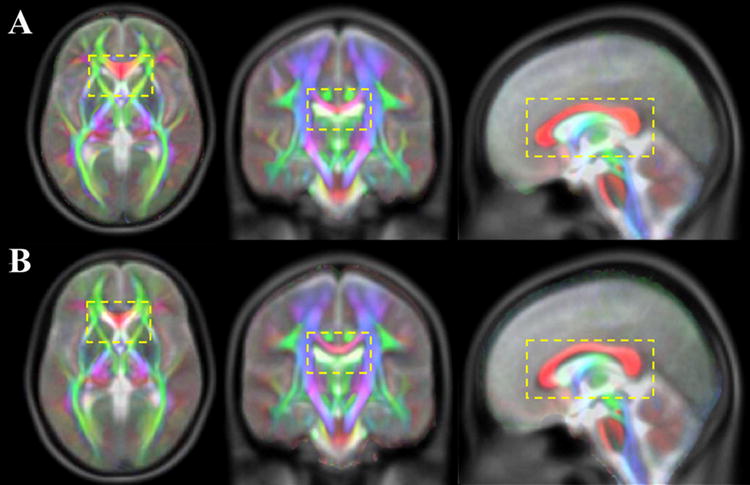

The cross-correlation between the average b=0 sec/mm2 images of the IIT2 template and the T2-weighted images of the ICBM-152 template was equal to 0.9784. The cross-correlation between the same images of the previously published IIT and ICBM-152 templates was slightly lower, at 0.9730. Although the difference in cross-correlation values was small, the matching of anatomical information was visibly improved between the IIT2 and ICBM-152 templates, compared to the IIT and ICBM-152 templates, especially in medial white matter structures such as the corpus callosum (Fig.10).

Figure 10.

Diffusion anisotropy color maps from the IIT2 (A) and IIT (B) templates overlaid on the corresponding T2-weighted images of the ICBM-152 template.

Temporary ICBM DTI templates were constructed during the development of both the IIT and IIT2 templates, by spatially normalizing the b=0sec/mm2 volumes of a selected dataset to the T2-weighted ICBM-152 volume. In the present study, this was achieved using a higher dimensional registration algorithm, provided by ART, compared to the algorithm used in the development of the original IIT template. The ability of ART to produce a more accurate inter-subject match of brain MRI images than several other registration techniques was shown recently (Klein et al., 2009). As a result, the temporary ICBM DTI template used in the development of the IIT2 template demonstrated an improved anatomical match with the ICBM-152 template. Consequently, the matching of anatomical information was improved between the IIT2 and ICBM-152 templates, compared to the IIT and ICBM-152 templates, especially in medial white matter structures (e.g. corpus callosum) (Fig.10).